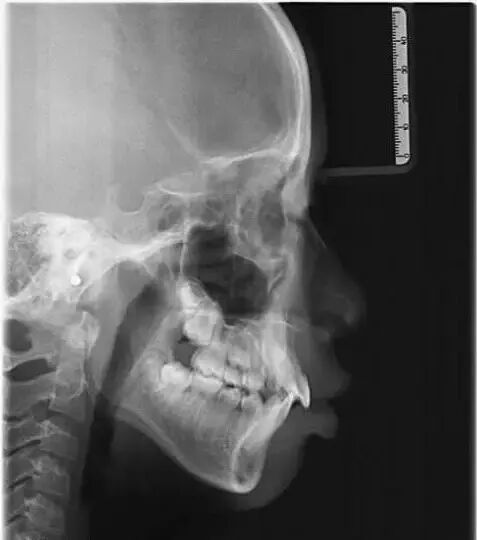

侧位片

可以判断上下颌骨之间的关系,比如上颌前突还是下颌后缩,颌骨与颅骨的关系,牙齿角度, 平面角度,脸长脸短,上面长还是下面长。